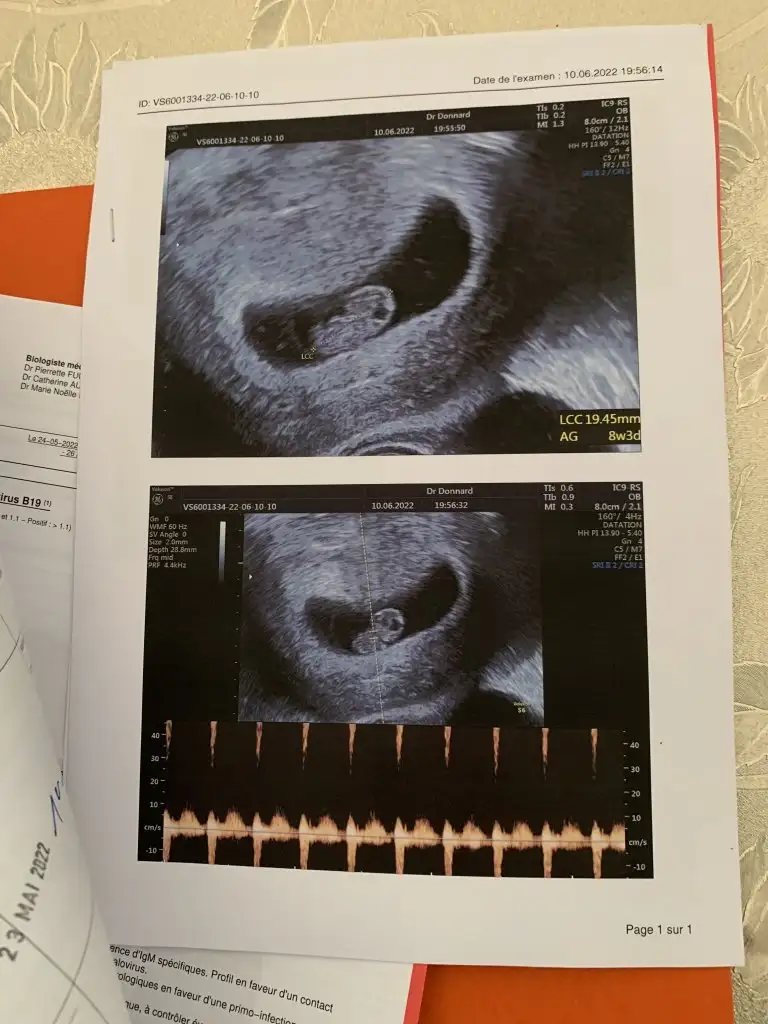

8+1 vajinal ultrason yorum yaparsanız sevinirim teşekkür ederimSelam Kızlarbir çok kişi gruplardan beni bilir. Yine yetiştim imdatlara

teoriye göre erkek ama bence prenses8+1 vajinal ultrason yorum yaparsanız sevinirim teşekkür ederim